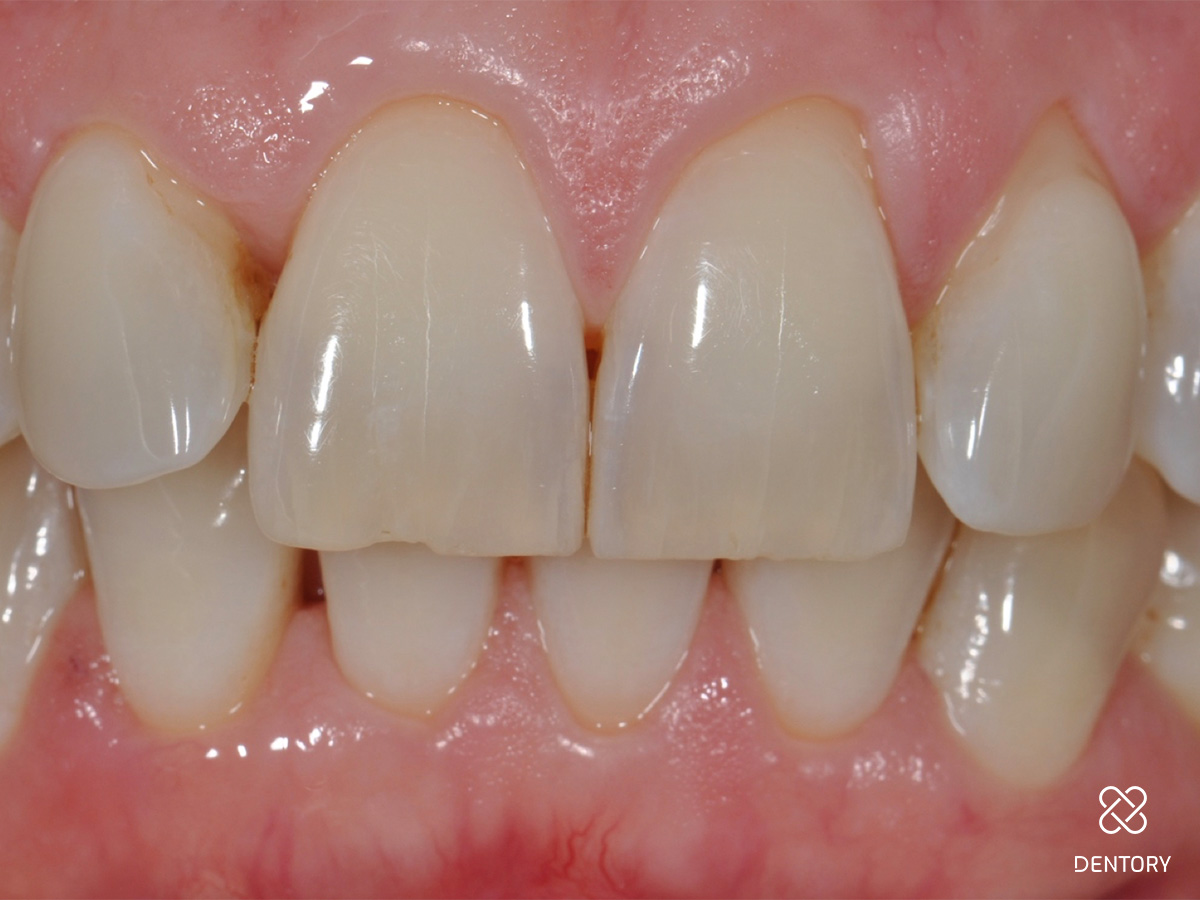

Abbildung 15

Die klinische Situation von frontal sechs Monaten nach dem chirurgischen Eingriff an 16 und 12 Monate nach initialer PA-Behandlung.